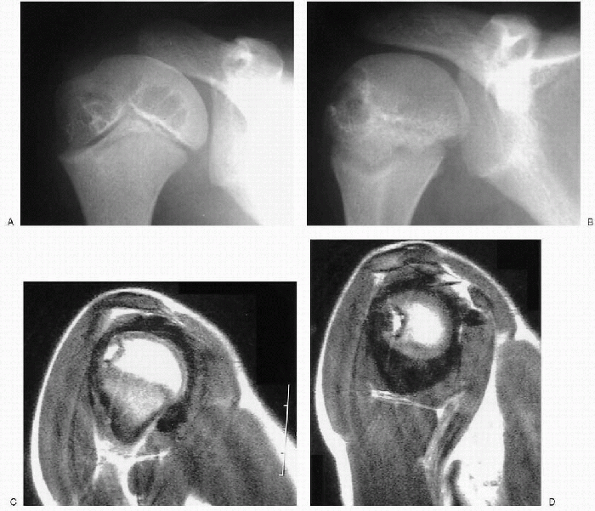

Hemosiderin deposits can be seen on MRI (Fig. 26.1-2), as can subchondral and intraosseous cysts or hemorrhage (Figs. 26.1-3 and 26.1-4).

Figure 26.1-4 Eight-year-old boy with factor VIII deficiency. (A and B) Anteroposterior plain x-rays of the shoulder show cyst formation in the humeral head. (C and D) Coronal magnetic resonance images reveal marked synovial hyperplasia and hemosiderin deposits, called a blooming appearance.